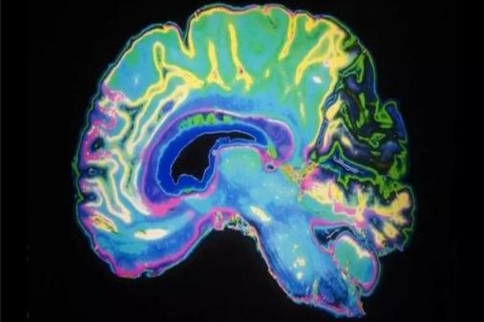

美國一項新研究發(fā)現(xiàn),被視為帕金森病“元兇”之一的一種蛋白其實也發(fā)揮著修復(fù)DNA(脫氧核糖核酸)斷裂損傷的關(guān)鍵功能,能幫助預(yù)防帕金森病患者的腦細胞死亡?;诖擞锌赡茉O(shè)計出帕金森病等大腦疾病的新治療方法。

帕金森病患者的典型癥狀包括手腳震顫、動作遲緩等,目前的醫(yī)療手段只能緩解癥狀,不能阻止病情發(fā)展,也無法病愈疾病。長期以來,阿爾法-突觸核蛋白在大腦中堆積成路易體團塊,導(dǎo)致腦細胞死亡或者阻礙腦細胞發(fā)揮正常作用,被認為是帕金森病發(fā)病的重要原因之一。

通過分析小鼠腦細胞和人類死者的腦組織,美國俄勒岡衛(wèi)生科學(xué)大學(xué)領(lǐng)導(dǎo)的一項新研究發(fā)現(xiàn),腦細胞的細胞核內(nèi)DNA發(fā)生斷裂后,阿爾法-突觸核蛋白會快速聚集到損傷部位開展修復(fù)工作。然而,如果這種蛋白以路易體團塊形式堆積在細胞核周圍的細胞質(zhì)中,DNA斷裂損傷會加劇。

研究人員認為,前沿發(fā)現(xiàn)說明阿爾法-突觸核蛋白在修復(fù)DNA斷裂方面發(fā)揮著關(guān)鍵作用。路易體團塊之所以會造成問題,是因為它將阿爾法-突觸核蛋白從腦細胞的細胞核中抽離到了細胞質(zhì)中。“打個比方說,如果阿爾法-突觸核蛋白是工廠的工人,這就好似工人們都跑去喝咖啡,而機器無人看管。”

研究負責(zé)人、俄勒岡衛(wèi)生科學(xué)大學(xué)醫(yī)學(xué)院神經(jīng)學(xué)副教授維韋克·溫尼在一份聲明中說,這是研究人員初次發(fā)現(xiàn)阿爾法-突觸核蛋白具有修復(fù)DNA斷裂的功能,而帕金森病等大腦疾病患者似乎缺乏這種修復(fù)功能,導(dǎo)致腦細胞大量死亡。希望這項發(fā)現(xiàn)能有助于設(shè)計出新治療方法,來替代阿爾法-突觸核蛋白的功能,或在帕金森病等大腦疾病患者身上增強這種蛋白的修復(fù)功能